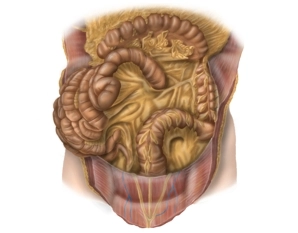

Colon descendente y colon sigmoide

![Colon descendente y colon sigmoide]()